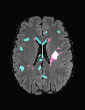

In recent years, data-driven machine learning (ML) methods have revolutionized the computer vision community by providing novel efficient solutions to many unsolved (medical) image analysis problems. However, due to the increasing privacy concerns and data fragmentation on many different sites, existing medical data are not fully utilized, thus limiting the potential of ML. Federated learning (FL) enables multiple parties to collaboratively train a ML model without exchanging local data. However, data heterogeneity (non-IID) among the distributed clients is yet a challenge. To this end, we propose a novel federated method, denoted Federated Disentanglement (FedDis), to disentangle the parameter space into shape and appearance, and only share the shape parameter with the clients. FedDis is based on the assumption that the anatomical structure in brain MRI images is similar across multiple institutions, and sharing the shape knowledge would be beneficial in anomaly detection. In this paper, we leverage healthy brain scans of 623 subjects from multiple sites with real data (OASIS, ADNI) in a privacy-preserving fashion to learn a model of normal anatomy, that allows to segment abnormal structures. We demonstrate a superior performance of FedDis on real pathological databases containing 109 subjects; two publicly available MS Lesions (MSLUB, MSISBI), and an in-house database with MS and Glioblastoma (MSI and GBI). FedDis achieved an average dice performance of 0.38, outperforming the state-of-the-art (SOTA) auto-encoder by 42% and the SOTA federated method by 11%. Further, we illustrate that FedDis learns a shape embedding that is orthogonal to the appearance and consistent under different intensity augmentations.